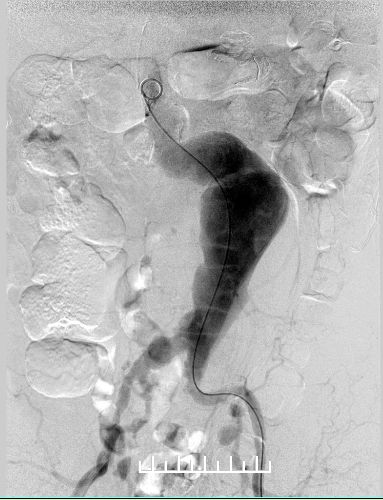

使用全穿刺技术(Preclose技术),建立双侧股动脉及右侧肱动脉入路。“全身像”显示:瘤颈成角约90度,左侧髂总动脉钙化扭曲严重,双侧髂内动脉显影,左侧髂内动脉瘤。

栓塞右侧髂内动脉,角度刁钻,使用翻山桥配合猪尾导管及超滑眼镜蛇,到达靶血管。8mm、6mm弹簧圈栓塞。

栓塞左侧髂内动脉。箭头处可见髂总动脉钙化扭曲明显,进出导管十分困难。

右肾动脉闭塞,精确定位左肾动脉开口释放支架。

左股动脉入路导丝超选短腿失败,经右侧肱动脉使用导丝穿针引线从股动脉引出。

左侧放置第一枚髂腿支架(16mm*140mm,美敦力)

左侧放置第二枚髂腿支架(16mm*140mm,美敦力)

右侧完全释放主体再接一枚16mm-14mm 髂腿支架于髂总动脉近段(美敦力)

Ib型内漏(远端漏),需要处理

左右分别使用13.5*80、13.5*60mmFluency延长。左侧支架一定要越过髂动脉弯曲处,否则容易闭塞。此处可以看到左侧支架远端稍微有弯曲折叠。